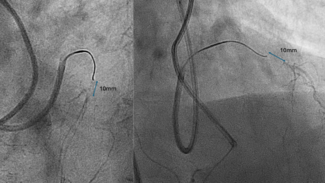

A 42-year-old man was admitted with an inferior ST-segment elevation myocardial infarction. Emergency coronary angiography revealed a critical lesion of the middle right coronary artery, which was treated with a 3.5 x 18-mm...

Video Supplement to "Intravascular Ultrasound Guided Management of Early Stent Thrombosis Secondary to Coronary Intramural Hematoma" (Clinical Image).